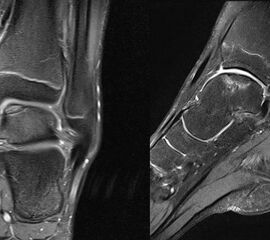

MRT

Die Kernspintomographie hat ihre Stärke in der Darstellung von Weichteilverletzungen. Insbesondere Verletzungen der Wachstumsfuge, des Periosts und der Bänder lassen sich gut visualisieren. Nachteilig ist die Untersuchungsdauer von 20-30 Minuten. Bleibt das Kind während dieser Zeit nicht ruhig liegen, kommt es zu Bewegungsartefakten, welche die Beurteilbarkeit der Bilder beeinträchtigen.

Osteochondrale Verletzungen können infolge eines Distorsionstraumas beobachtet werden (Taluskantenfraktur), teilweise lässt sich auch kein Trauma eruieren. Der es sich bei osteochondralen Verletzungen um keine Arthrose handelt, ist gerade bei Schmerzfreiheit ein defensives Vorgehen angezeigt. Bei offenen Wachstumsfugen kann eine osteochondrale Verletzung unter konservativer Therapie ausheilen.

Eine retrograde Anbohrung ist indiziert, wenn sich im MRT Verlauf eine zunehmende Sklerosierung im Randbereich der Läsion zeigt bei intakter Knorpeloberfläche.

Instabile Knorpelareale werden arthroskopisch entfernt in Verbindung mit einer Mikrofrakturierung der subchondralen Knochenlamelle.